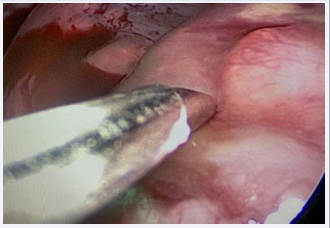

It was agreed in this discussion to perform Fine Needle Aspiration Biopsy (FNAB) of the right lung lesion under ultrasound control, which showed positive results for malignant cells, also with inflammatory elements, lymphocytes and nuclear polymorphism. The antibiotic therapy was changed to intravenous Vancomycin and Meronem and it was then decided to perform a biopsy of the lung tumor lesion, via thoracoscopy, which was performed in the operating room on February 27, 2023 (Figures A,B).

Figure B Image showing the thoracoscopic biopsy of the tumor.

Figure B: Image showing the thoracoscopic biopsy of the tumor.